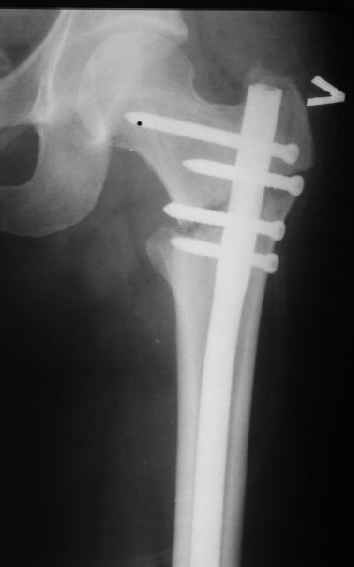

При межвертельных переломах с цефаломедуллярными гвоздями бывает, что проксимальый винт проходит или черед периферический отломок, или прямо над ним. И если остался диастаз, то этот винт при осевой нагрузке не дает сблизиться отломкам. Пример такого остеосинтеза в застарелом случае в приложении.

В качестве предупреждающей меры можно долотом разрушить латеральную стенку дистального отломка под винтом.

Картинка красивая, но на мой взгляд, не совсем оптимальная: Слишком медиально введён стержень - риск аваскулярного некроза головки бедра.

расположении сопредельных отломков- хорошая локальная васкуляризация. В приведённом случае я бы предпочёл принцип межфрагментарной компрессии (рекон/гамма нэйл 130- 135) принципу шинирования перелома.

Женя, эта картинка показывает не оптимальное лечение вертельных переломов в моем представлении, а особенности дизайна упомяутого фиксатора.

В частности, его возможности при фиксации переломов проксимального отдела бедра - в сравнении с другими, имеюшими лишь по одному статическому и динамическому отверстию и с кондуктором для введения 2 винтов.

Это было года 2,5 назад, мы тогда еще уточняли возможности шинирования с угловой стабильностью гвоздем с поперечным расположением винтов при переломах проксимального отдела бедра. Пациенту не пришлось приобретать намного более дорогой рекон или проксимальный гвоздь. В приложении еще несколько примеров применения того гвоздя при высоких переломах бедра, в том числе с более латеральной точкой входа. Гвоздь изгибаем для этого.